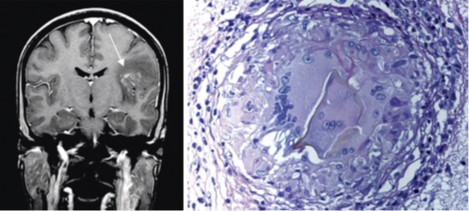

Panel D

A CT scan of the brain of a young Brazilian woman who presented with seizures and a headache two months after bathing in a fresh water lake.The study shows a conglomerate of nodules enhanced by contrast (arrow, left image). Her brain biopsy showed well-formed granulomas surrounding S. mansoni eggs (representative granuloma, right image).